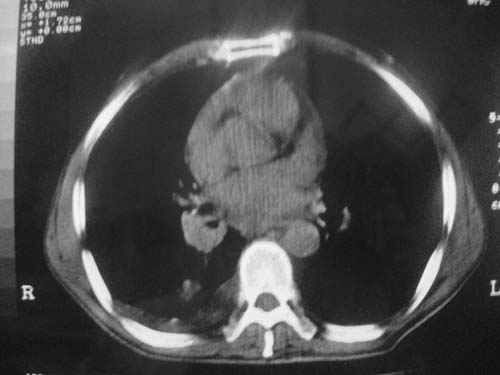

以下是引用科室第一人在2010-3-25 20:30:00的发言:[br]1:纵膈肿瘤性病变,恶性胸腺瘤可能性大伴纵膈右肺门淋巴结转移,右侧胸腔积液。[br]2:右侧肺门肿瘤性病变,纵膈淋巴结转移,右侧胸腔积液。右下叶转移。

以下是引用子期在2010-3-25 21:00:00的发言:[br]先考虑右中央型肺癌伴转移。

以下是引用江广1996在2010-3-25 22:49:00的发言:[br]通常肺癌向纵隔转移多见,纵隔肿瘤向肺内转移少见(有的表现为向肺内侵润)。本例以一元论考虑:右中心型肺癌并纵隔淋巴等多处转移。[br][br][本贴已被 江广1996 于 2010-3-25 22:50:07 修改过]

以下是引用yangyudong333在2010-3-26 6:43:00的发言:[br]“冰冻纵膈”,考虑纵膈淋巴瘤伴肺内及胸膜侵润。